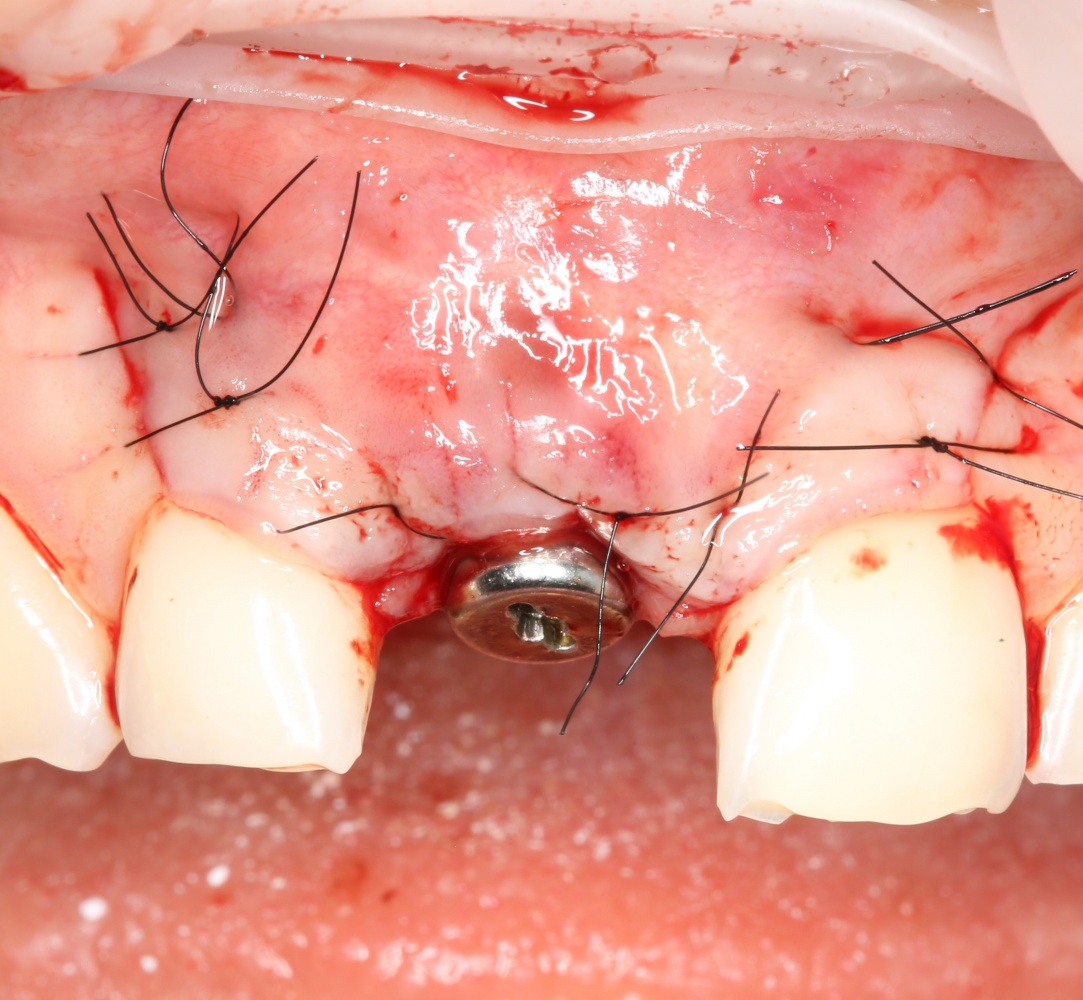

Проводя остеопластику, мы не забываем о «факторах успеха остеопластических операций«, в частности о факторе #3. Поэтому, несмотря на то, что «классикой» немедленной имплантации является установка формирователя десны, мы перекрываем лунку клыка барьерной мембраной и ушиваем ее наглухо:

Через 4 месяца клиническая ситуация выглядит подобным образом:

мы можем спокойно приступить к формированию десны: